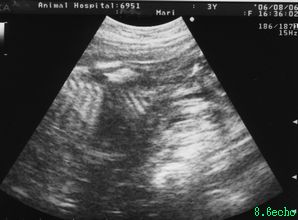

妊娠55日目

体重が100g増え3.2kgになりましたが まりの食欲の無さを心配してくれた獣医さんから電話を貰い 念の為エコーで胎児の様子を確認してみることにしました

今回も胎児2頭が映り 心臓の動き、血流も確認され 背骨や手足の様子も分かります 少ない栄養でもここまで育ってくれているんだと感激しましたが このままだと生まれる仔犬は80g位にしかならないだろうと言われ愕然としてしまいました

出産予定日まで後一週間余りですので何が何でも食べさせなければと気を取り直します 朝晩の体温は37.6度まりの平熱です